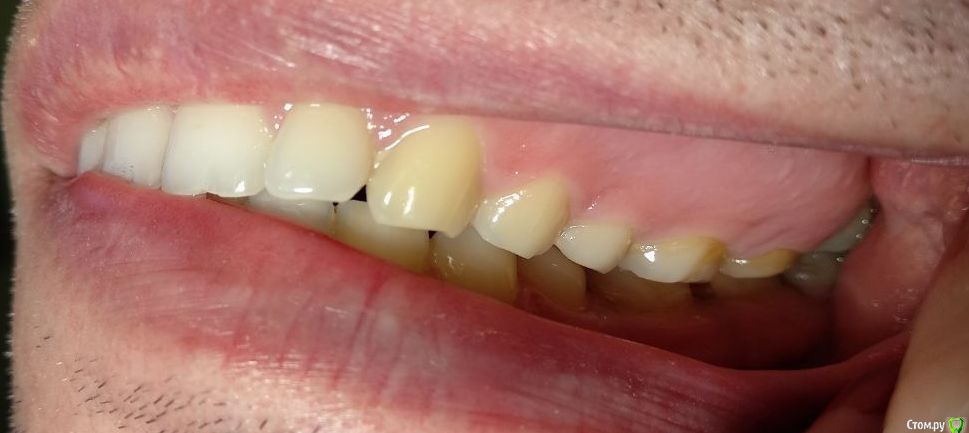

Здравствуйте! Откололся кусок зуба. 8 октября сделали КЛКТ (3Д снимок всех зубов). Вскрыли зуб, была проведена девитализация. Поставили диагноз: хронический фиброзный пульпит 37 зуба. 18 октября было проведено первичное лечение 3-х канального зуба эндомотором с использованием микроскопа и системы коффердам. Все каналы были запломбированы гуттаперчивыми штифтами на силлере методом латеральной конденсации Adseal, внутрь заложена ватка и поставлена временная пломба дентин-паста. 29 октября ортопед №1 посмотрел прицельный снимок (см. снимок зуба 2) и сам зуб, пломбу не снимал. Озвучил, что у меня низкая высота зуба, мне нужно установить культевую кобальт-хромовую вкладку и сверху покрыть металлокерамической коронкой зуб. Также сказал, что циркониевая вкладка мне не подходит из-за высоты. Однако, поскольку ортопед №1 уходил на обучение, мне было предложено обратиться в другую клинику к другому ортопеду. 1 ноября ортопед №2 посмотрев мой зуб без снимка заявил, что у меня сохранились три стенки у зуба и мне надо просто закрыть пломбой этой зуб. Поскольку ортопед №2 предложил диаметрально противоположное лечение зуба, то я решил обратиться в третью клинику. Ортопед №3 посмотрев снимок моего зуба, сам зуб, в том числе внутри (снял мою временную пломбу из дентина), заявил, что у меня низкая высота зуба и мне нельзя ставить культевую вкладку и коронку. И было предложено сделать вкладку из пресс керамики overlay. Также когда удалили временную пломбу у меня увидели кариес на этом зубе. В конце приема мне взамен снятой пломбы установили временную пломбу парасепт.

Сделал несколько фотографий, тк не совсем понял с какого ракурса делать фото с сомкнутыми зубами.